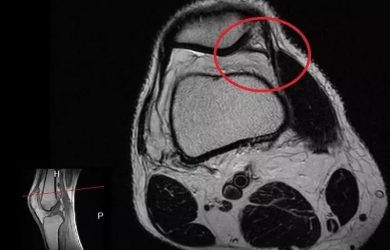

Артроскопічна резекція медіопателярної складки колінного суглоба (синдром медіопателярної складки, гіпертрофія медіопателярної складки) 1. Медіопателярна складка 2. Передня хрестоподібна